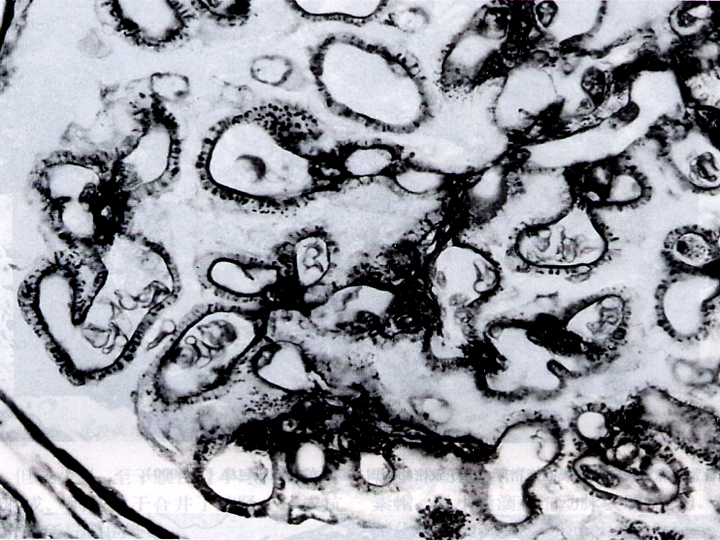

轻微肾小球病变 (minimal change disease) 也称轻微病变性肾小球肾炎(minimal change glomerulonephritis),是一种常见的肾小球疾病,病理特点是光镜下肾小球无明显变化,电镜下肾小球上皮细胞足突融合(如下图),临床特点是大量蛋白尿或肾病综合征。好发于儿童和青少年。

(电子显微镜下可见:肾小球上皮细胞足突融合)

(1)病理变化 :光镜下肾小球无病变或仅见局灶节段性轻度异常。近端肾小管上皮细胞内可见脂滴空泡,故又称脂性肾病(lipoid nephrosis)。

免疫荧光: 肾小球内无免疫球蛋白和补体沉积。

电镜 肾小球基底膜和系膜无显著变化,肾小球内无电子致密沉积物,主要变化是肾小球上皮细胞足突融合,故有人称之为足突病(foot process disease)。